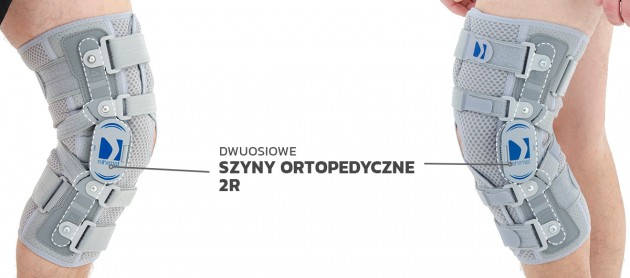

Orteza przeciwprzeprostna typu otwartego EB-SK/P jest profesjonalnym wyrobem medycznym kl. I poprawiającym wydolność chodu, służącym do mocnej stabilizacji stawu kolanowego i likwidacji tendencji do przeprostu stawu. Została wykonana ze strukturalnego surowca ProSIX. Boczne części ortezy zostały wykonane z nowego innowacyjnego surowca Active 3D. Wyrób został wyposażony w aluminiowe szyny boczne, które stabilizują staw kolanowy w pozycji bocznej. Posiadają one konstrukcję dwuosiową, zbliżoną do anatomicznego ruchu w stawie kolanowym oraz wyposażono je w mechanizm zębaty, równomiernie poruszający każde z ramion szyny. Dodatkowo szyny wyposażono w pasy przeciwprzeprostne, nie zamykające się w pełnym okręgu, co gwarantuje prawidłowe krążenie krwi. Każda z szyn posiada silikonowe, anatomicznie wyprofilowane poduszki dodatkowo bocznie stabilizujące staw kolanowy. Wyrób posiada również taśmy obwodowe pozycjonujące ortezę na kończynie.